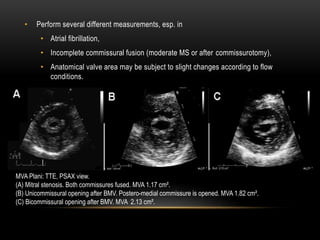

• Perform several different measurements, esp. in

• Atrial fibrillation,

• Incomplete commissural fusion (moderate MS or after commissurotomy),

• Anatomical valve area may be subject to slight changes according to flow

conditions.

MVA Plani: TTE, PSAX view.

(A) Mitral stenosis. Both commissures fused. MVA 1.17 cm².

(B) Unicommissural opening after BMV. Postero-medial commissure is opened. MVA 1.82 cm².

(C) Bicommissural opening after BMV. MVA 2.13 cm².